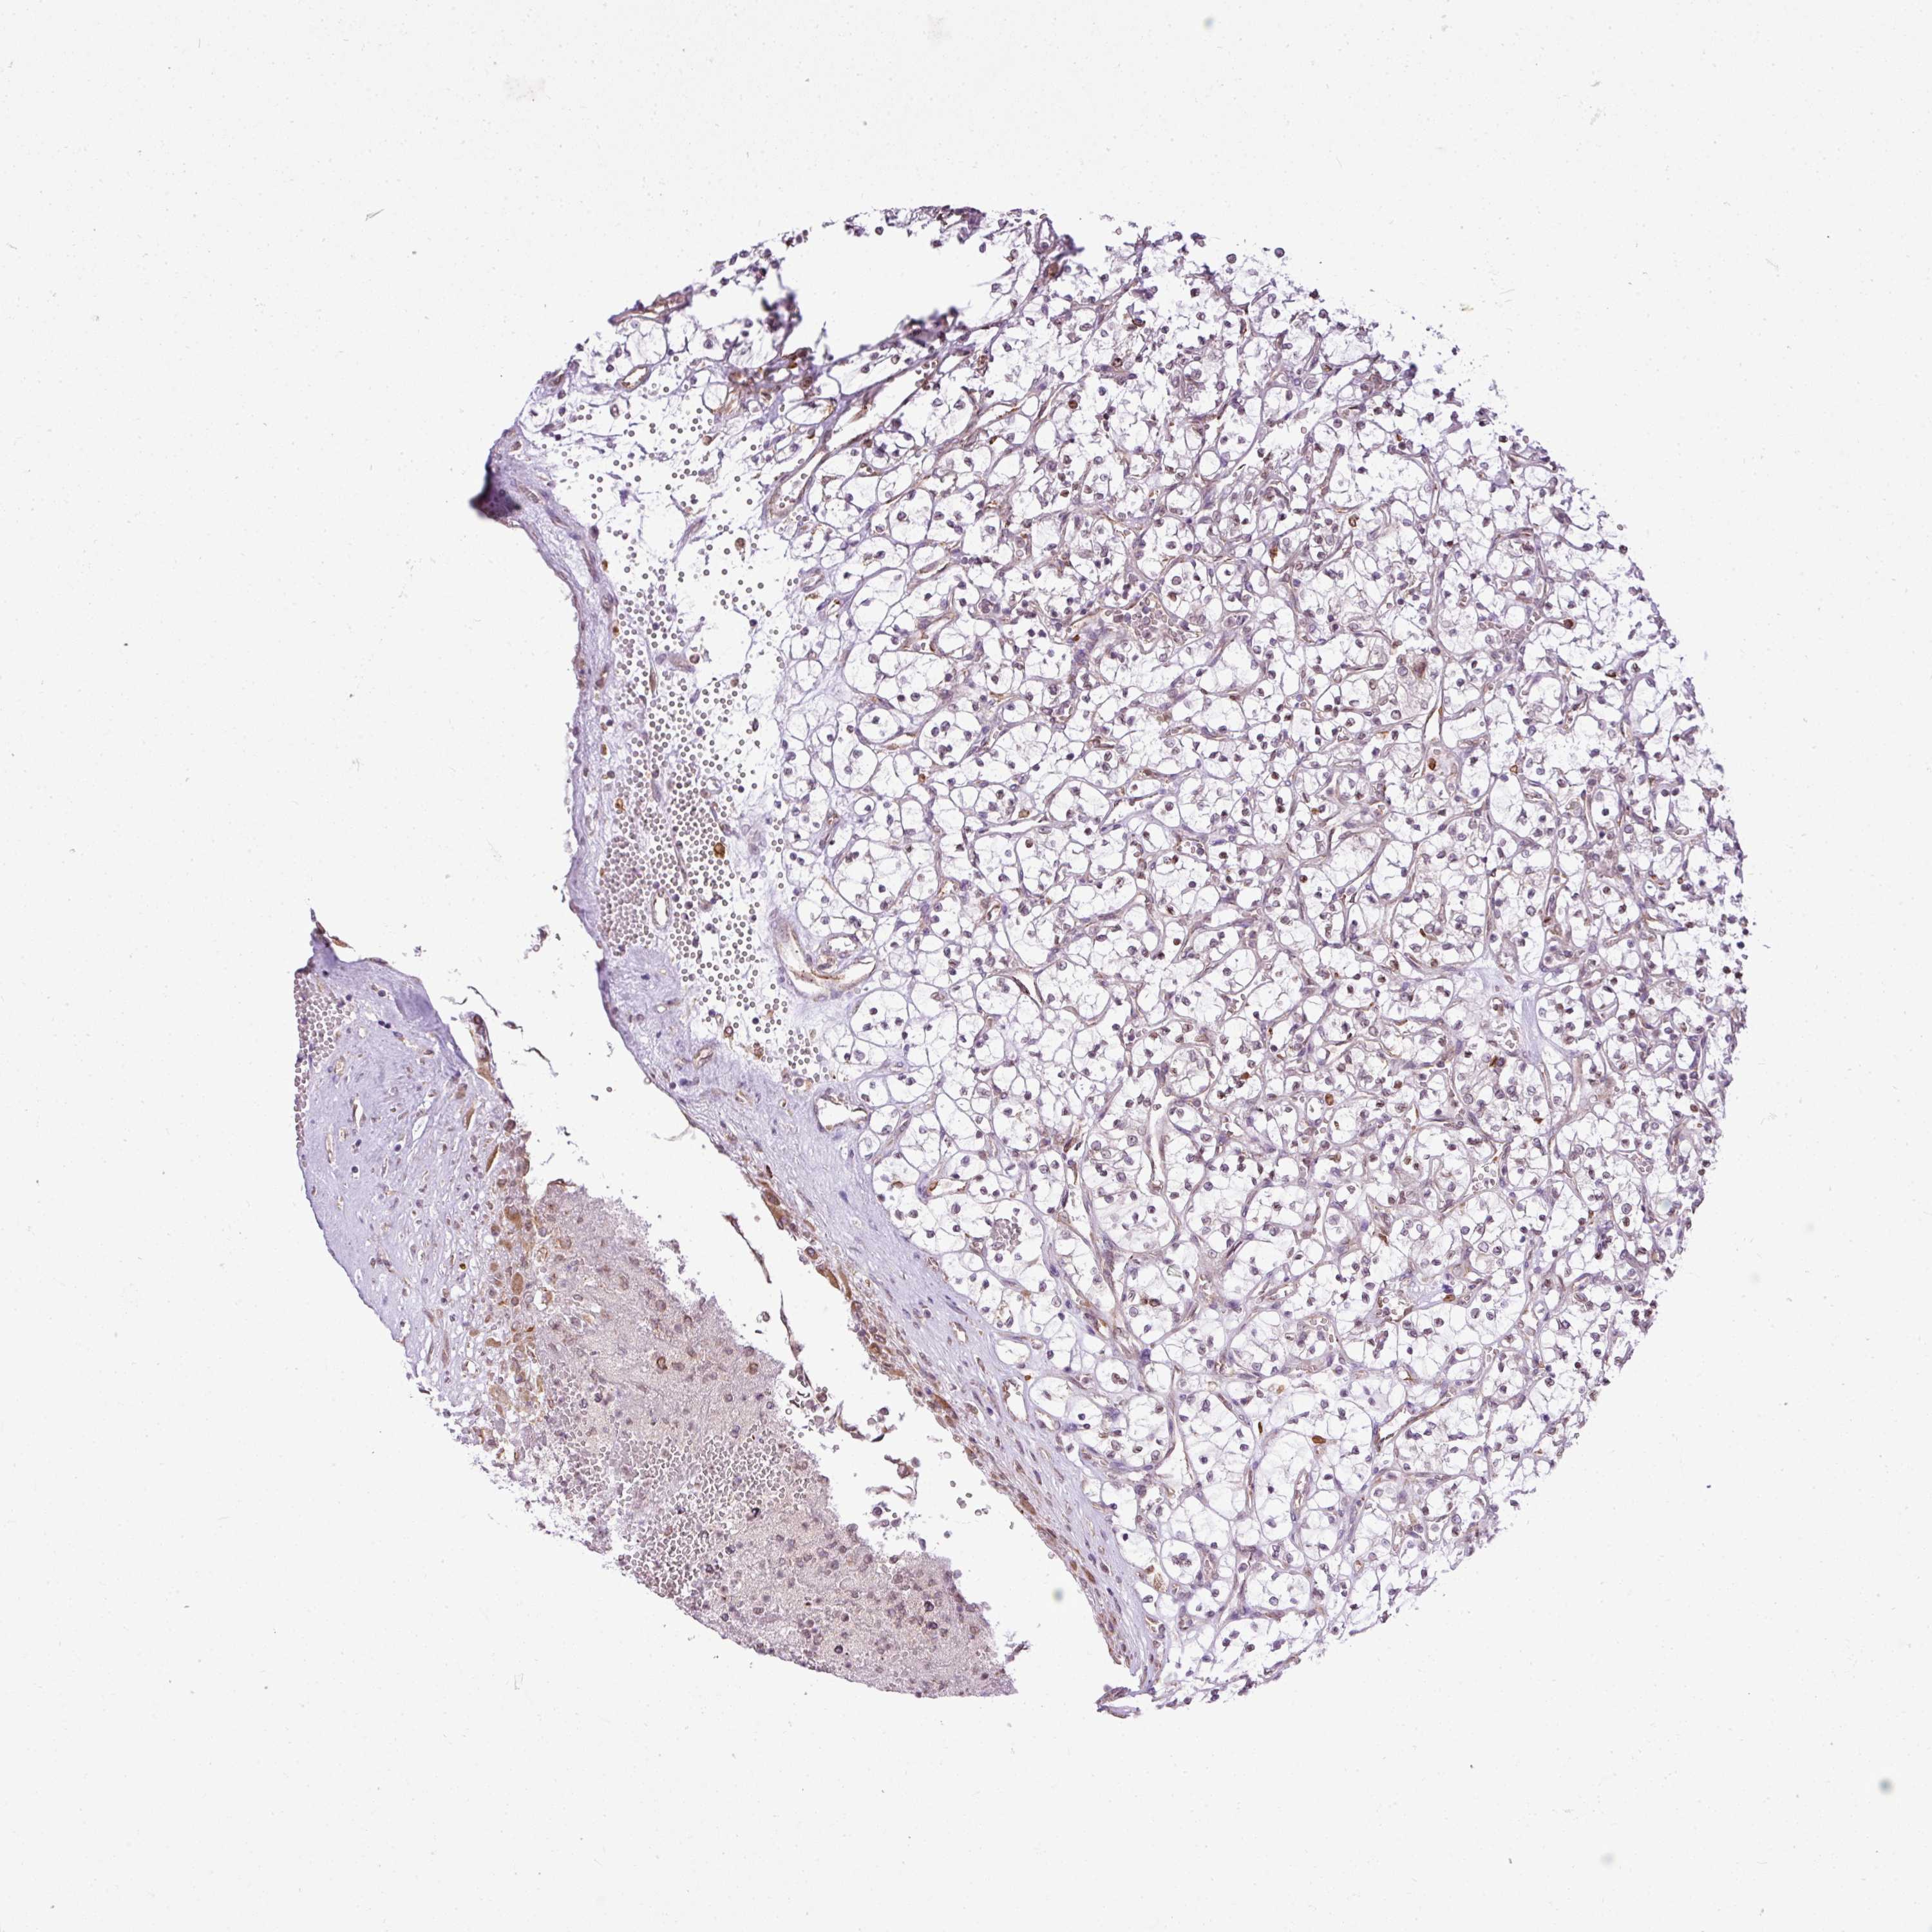

KIDNEY RENAL PAPILLARY CELL CARCINOMA (TCGA) - Interactive survival scatter ploti

The Survival Scatter plot shows the clinical status (i.e. dead or alive) for all individuals in the patient cohort, based on the same data that underlies the corresponding Kaplan-Meier plots. Patients that are alive at last time for follow-up are shown in blue and patients who have died during the study are shown in red.

& Survival analysisi

Kaplan-Meier plots summarize results from analysis of correlation between mRNA expression level and patient survival. Patients were divided based on level of expression into one of the two groups "low" (under cut off) or "high" (over cut off). X-axis shows time for survival (years) and y-axis shows the probability of survival, where 1.0 corresponds to 100 percent.

COX18 is not prognostic in Kidney Renal Papillary Cell Carcinoma (TCGA)